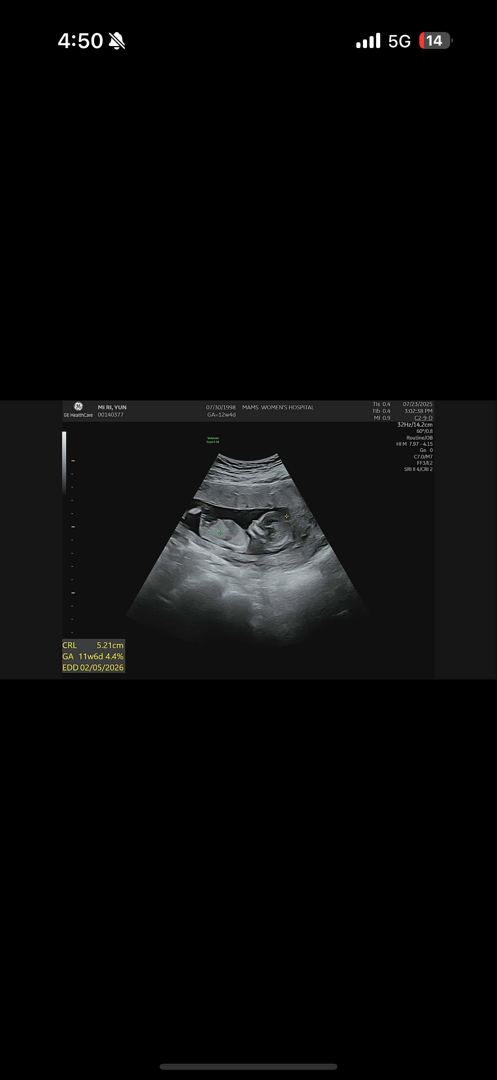

각도법 봐주세용!

아들일까용 딸 일까용?

생식기가 잘 안보이는 각도같긴한데...아들같아보여용 사진으론